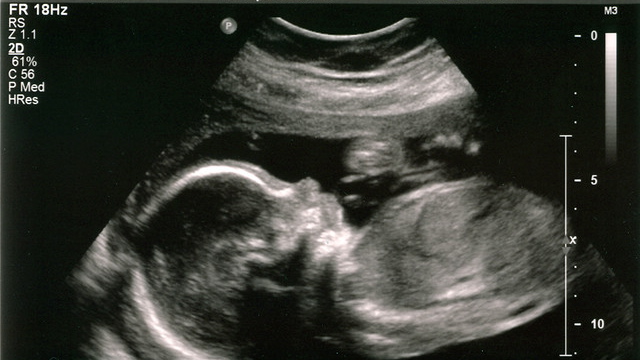

Denne gangen skal jeg skrive om noe som er vanskelig å skrive om. Temaet er abort og konsekvensen er liv eller død. Jeg skrev en gang om hvor unik du er skapt. Jeg nevnte at da du bare var 3 uker gammel begynte hjertet ditt å slå. 6 uker gammel begynte armene og hendene dine å utvikle seg, samtidig som du fikk antydninger til fingre. Etter 11 uker var du ca. 7 cm lang, og da du var 16 uker begynte du kanskje å suge på tommelen? Slik er det altså med et foster som blir skapt og som utvikler seg i mors mage. Fra uke til uke skjer det nye ting, og selv om et lite foster lenge ligner på en reke, er det tidlig tegn til menneskeliv.

Etter 11 uker var du ca. 7 cm lang, og da du var 16 uker begynte du kanskje å suge på tommelen?

Abort er en avbrytelse av svangerskapet og det skilles mellom to typer aborter. Den ene er spontanabort som også kalles naturlig abort. I dette tilfellet frastøter kroppen fosteret og på den måten blir svangerskapet avbrutt. Den andre typen abort, er fremprovosert abort, hvor man avbryter svangerskapet ved hjelp av hjelpemiddel som legemidler og kirurgiske inngrep. Svangerskapsavbrudd kan foretas både før og etter at fosteret er levedyktig utenfor moren.